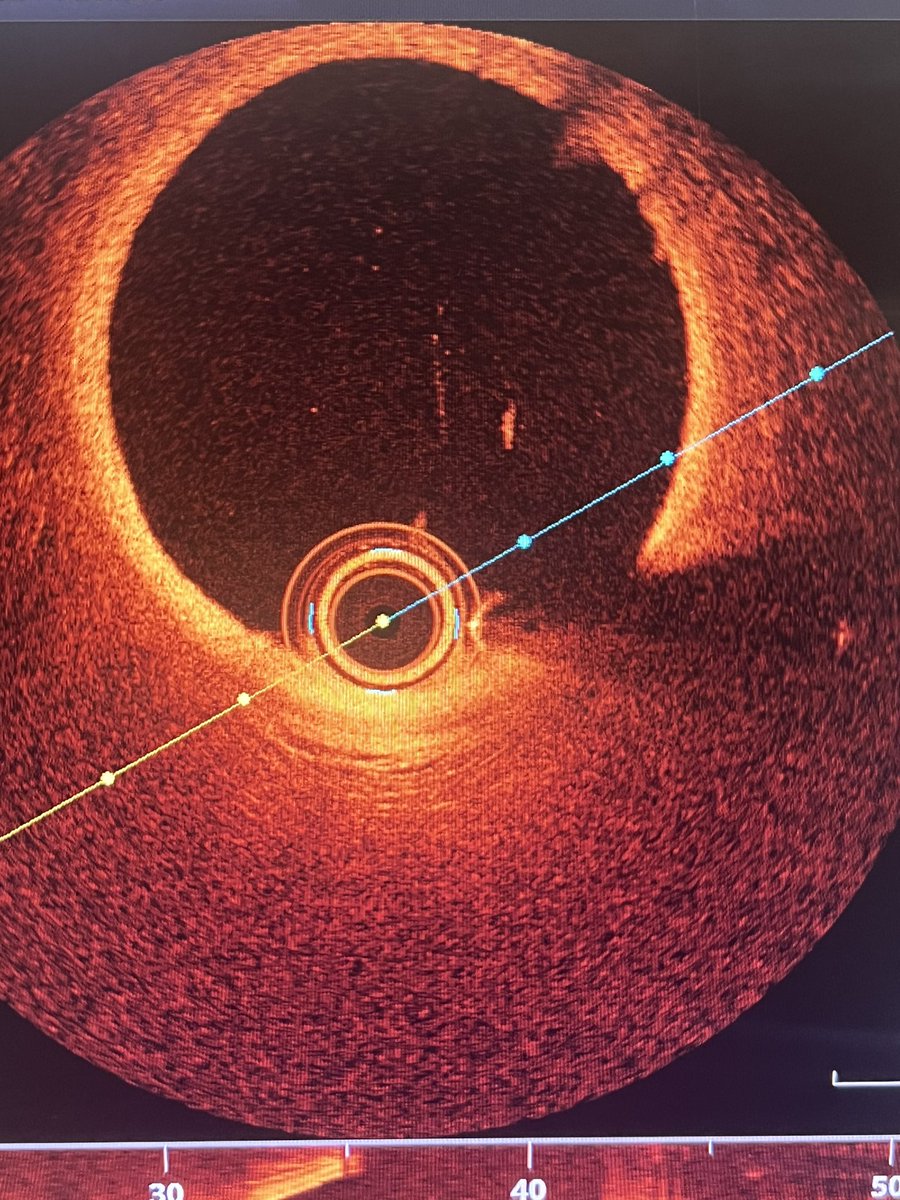

A 63 y.o female presented with NSTEMI. One year before CTA with normal LAD/RCA and mild lesion in OM1. Here is the angio and OCT images. What would you do?